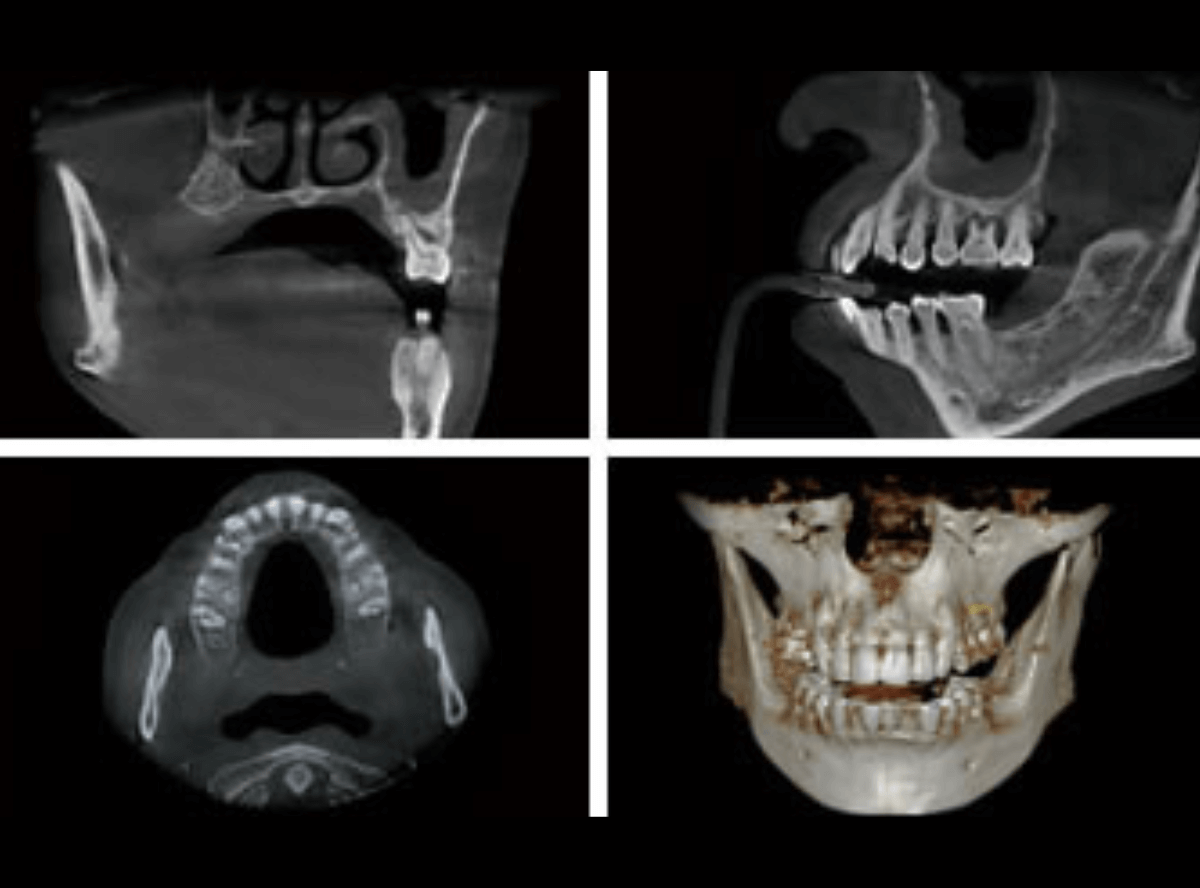

CT撮影による、審査・診断

インプラント治療において、CT撮影は不可欠です。

インプラントを安全に埋入するには、顎の骨の厚みや密度、神経や血管の走行を把握することが必要になりますが、レントゲンだけではこれらを全て把握することはできません。

CT撮影することにより、今までのレントゲン写真では得ることができなかった情報を得ることができ、より的確な診断が可能になります。

このCT撮影によって得られた情報(主に骨の厚みや幅)を元に、インプラント治療の可否を診断します。

場合によっては、インプラント治療が不可能という診断になる場合もありますので、ご了承ください。